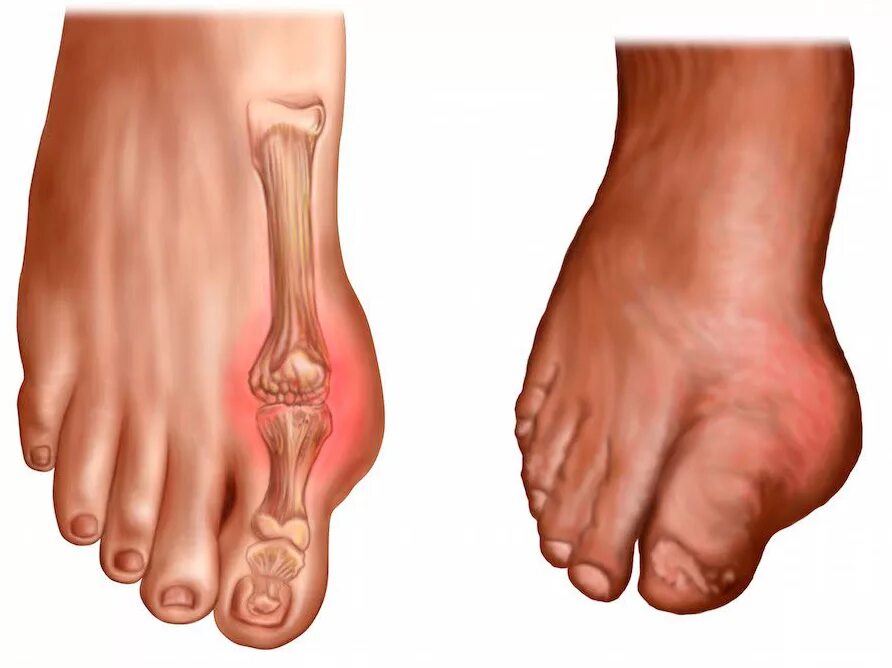

Подагра суставов стопы